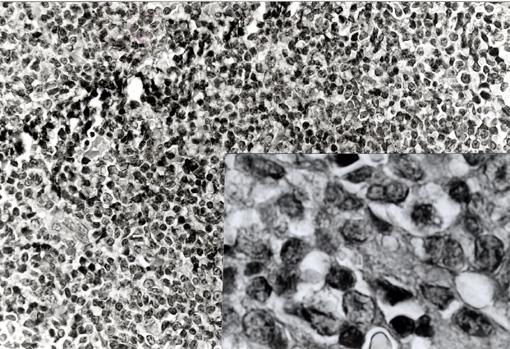

Criteria of Hist.ClassificationMalignant Lymphoma/Malignant lymphoma

LocationLarge intestine(Colon)/Sigmoid colon

Technique, MethodHistology

Size15 - 19